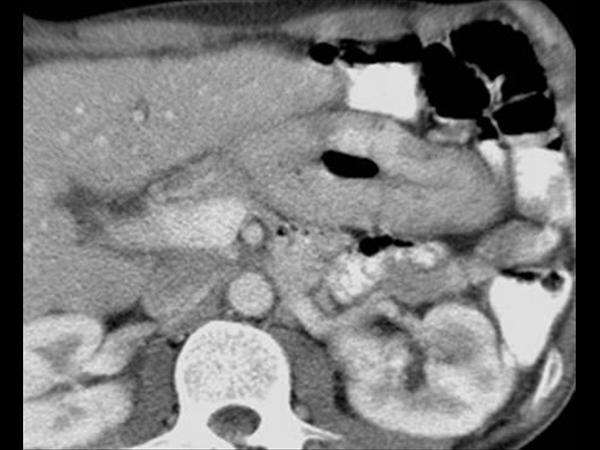

U dạ dày

» Thông tin: Nam giới – 41 tuổi.

» Lâm sàng: Đau thượng vị / Sút cân.